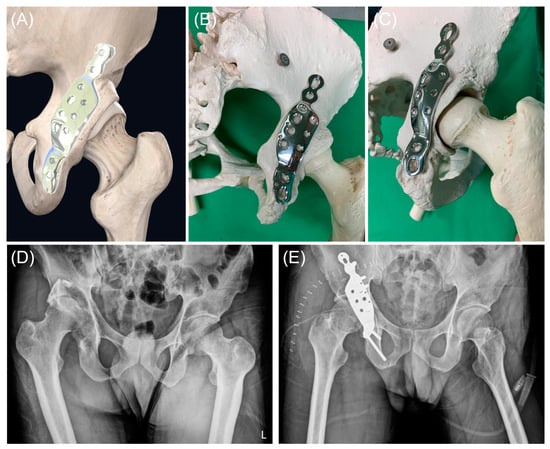

2.3. Implant Design